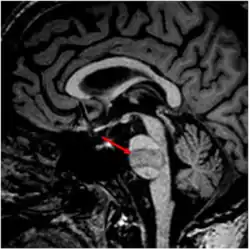

• МРТ человека с инфарктом головного мозга в области моста мозга (указан стрелкой), вследствие тромбоза базилярной артерии, у которого развился синдром запертого человека.